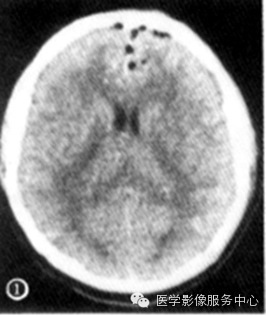

答案A,正確。本圖中患者全結腸擴張明顯,以脾區為重,腸腔超過6cm,符合中毒性巨結腸表現。雙側膈下可見遊離氣體,提示腸穿孔。結合患者以結腸充氣擴張為主,無小腸擴張,結腸腸壁毛糙,結腸袋結構不明顯,考慮患者為重症潰瘍性結腸炎,合並出現中毒性巨結腸及腸穿孔可能性大。答案B,錯誤。腸梗阻表現為梗阻近端腸管擴張,根據不同梗阻部位可出現雙泡症、小腸擴張、氣液平等,但單純結腸擴張而無小腸擴張者較難以腸梗阻解釋。答案C,錯誤。十二指腸潰瘍可穿孔出現膈下遊離氣體,較少出現結腸改變。答案D,錯誤。腸結核以回盲部最易受累,可有穿孔、梗阻等表現,但較少出現中毒性巨結腸。

如圖可見患者全結腸充氣擴張,尤以橫結腸及降結腸充氣擴張顯著,乙狀結腸較明顯充氣擴張,結腸袋結構不明顯,腸腔管壁邊緣較毛糙,雙側膈下可見遊離氣體。